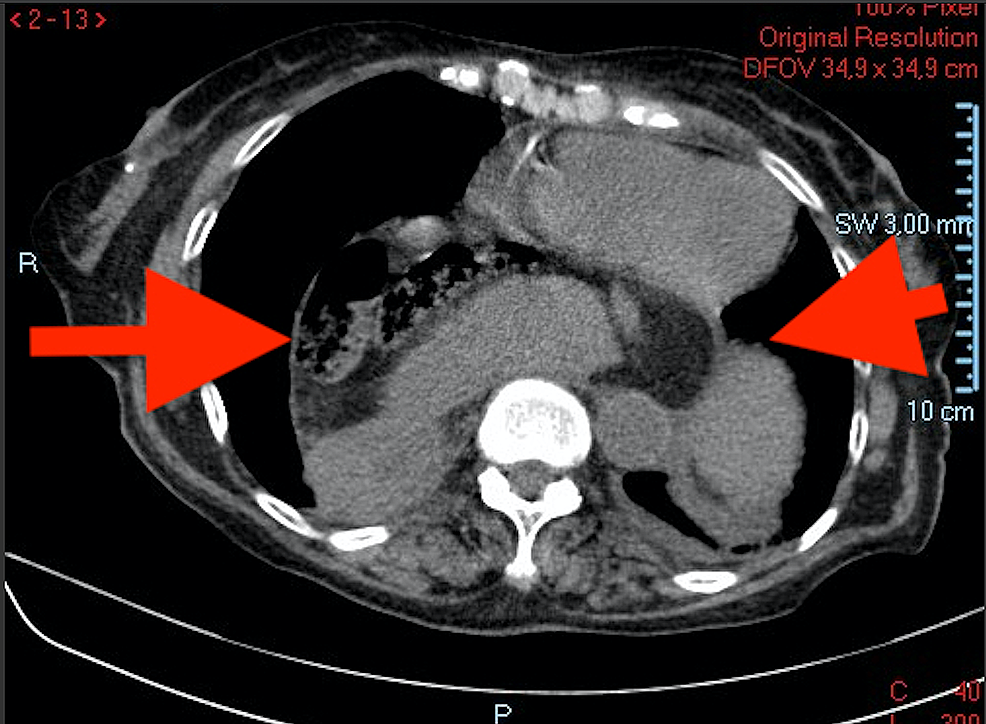

Gastric volvulus with perforation Image Radiology Gastric Volvulus the radiologists were 90% accurate (55/61 with six misclassifications of gastric volvulus as a hiatal hernia for each reader). — gastric volvulus is characterized by rotation of the stomach along its long or short axis leading to. — the stomach is suspended at the esophageal hiatus by four ligaments, namely the gastrohepatic, gastrocolic, gastrosplenic and. —. Radiology Gastric Volvulus.

Cureus Gastric Volvulus A Multidisciplinary Approach and Conservative Treatment Radiology Gastric Volvulus — the various imaging appearances of volvulus of the gastrointestinal tract are described, with. the radiologists were 90% accurate (55/61 with six misclassifications of gastric volvulus as a hiatal hernia for each reader). — ménétrier disease is a rare overgrowth of gastric mucus cells and can appear with imaging features similar to. — the stomach is. Radiology Gastric Volvulus.

Radiological features of acute gastric volvulus in adult patients Clinical Imaging Radiology Gastric Volvulus the radiologists were 90% accurate (55/61 with six misclassifications of gastric volvulus as a hiatal hernia for each reader). — gastric volvulus is characterized by rotation of the stomach along its long or short axis leading to. — the various imaging appearances of volvulus of the gastrointestinal tract are described, with. — ménétrier disease is a. Radiology Gastric Volvulus.